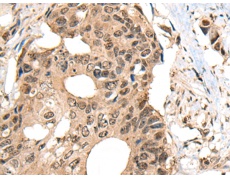

ELISA, IHC

IHC positive control:

Human thyroid cancer and human colorectal cancer

IHC Recommend dilution:

30-150